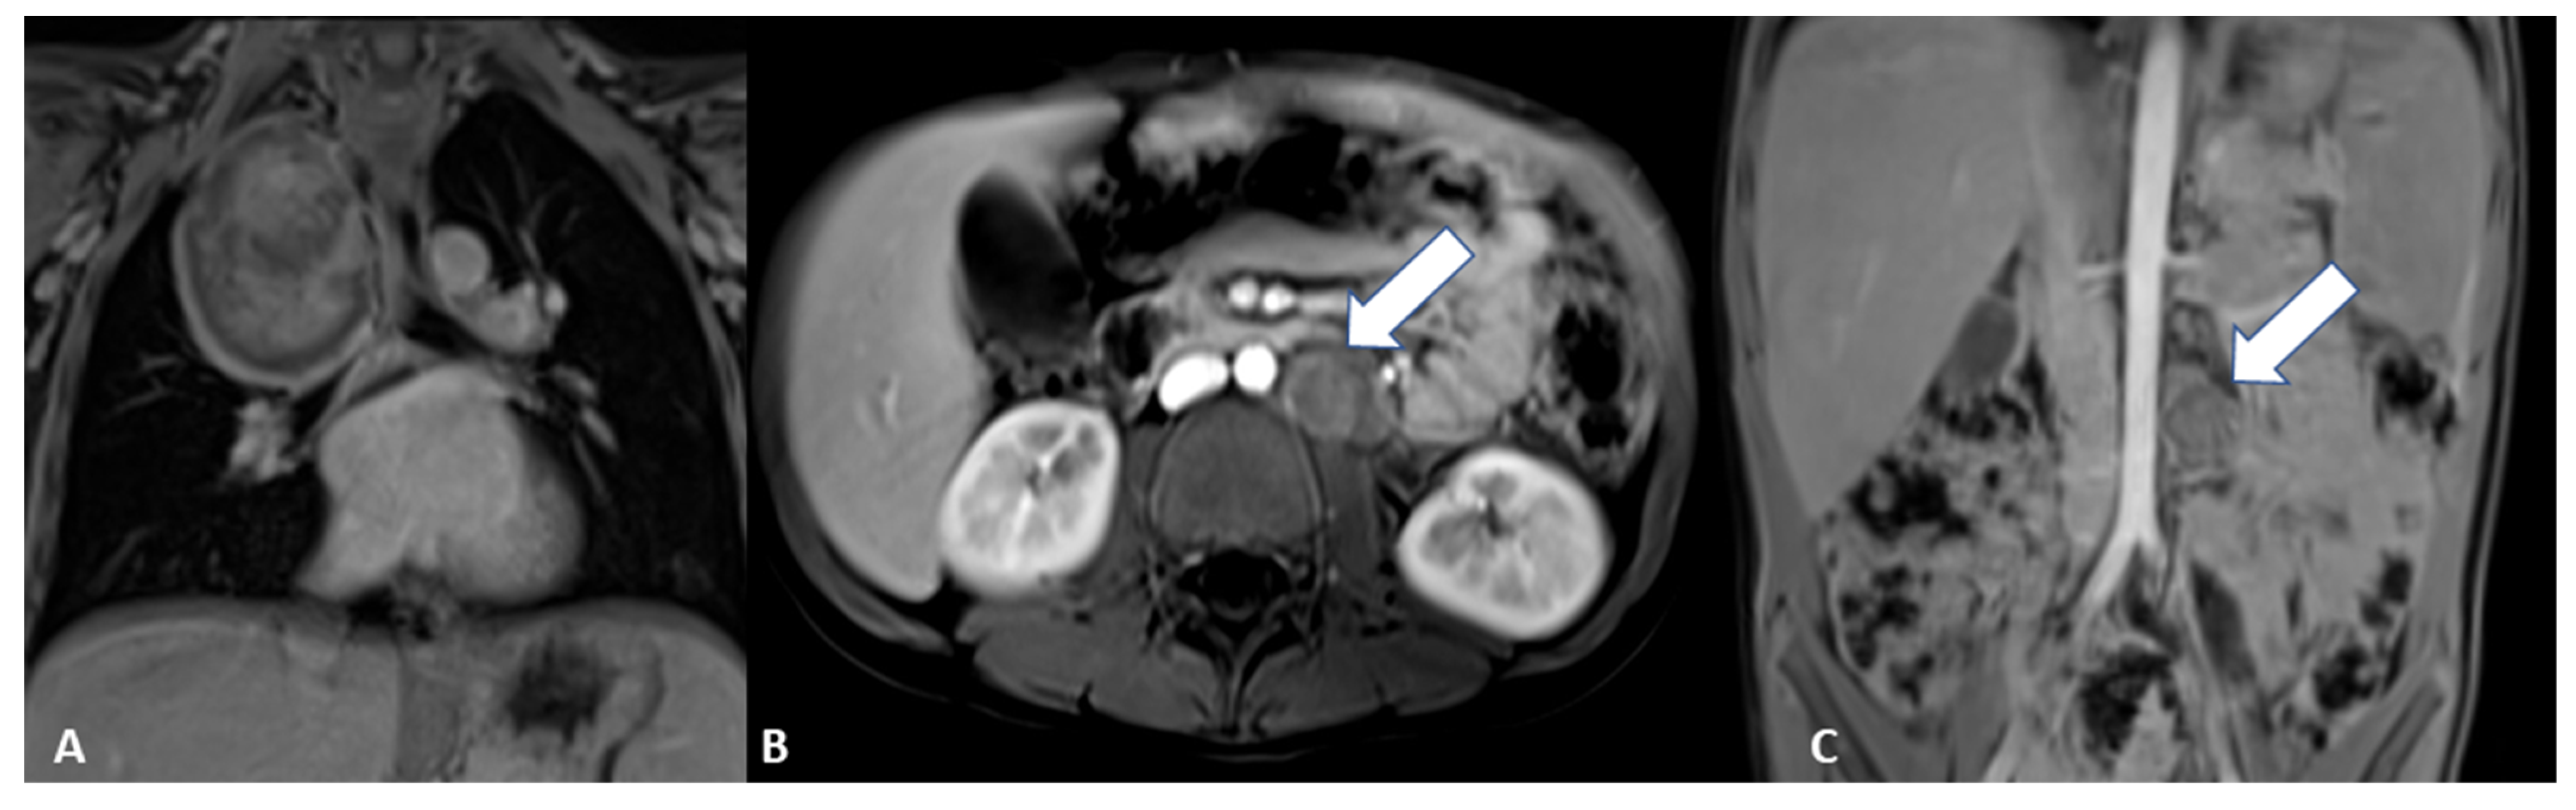

Figure 2. Magnetic resonance imaging (MRI) at baseline. The exam was performed in order to complete the framing and precisely define the anatomic relationships, which confirmed the two clear-edged, capsular, expansive formations located in the posterior mediastinum and in the left anterior paravertebral abdominal site, in the absence of intraspinal extension. An axial T2-weighted image shows the abdominal paravertebral mass (A) that presents inhomogeneous enhancement after contrast administration (B). The thoracic lesion in the posterior mediastinum shows a similar perfusion pattern, as shown in the coronal and sagittal T1-weighted images (E,F). (C) MRI axial diffusion-weighted imaging (DWI) shows a hyperintense rounded area with low apparent diffusion coefficient (ADC) value in the upper portion of the abdominal mass, as shown in (D) (arrow). Blood tests and urinary catecholamines were within normal limits. In order to determine a diagnosis of certainty, an echo-guided biopsy of the lesion located at the level of the posterior mediastinum was performed, as it was more easily reached than the abdominal mass; histopathological features were finally consistent with a GNBI, with the presence of Schwannian stromal development occupying >50% of tumor tissue [1] (see also histological image).